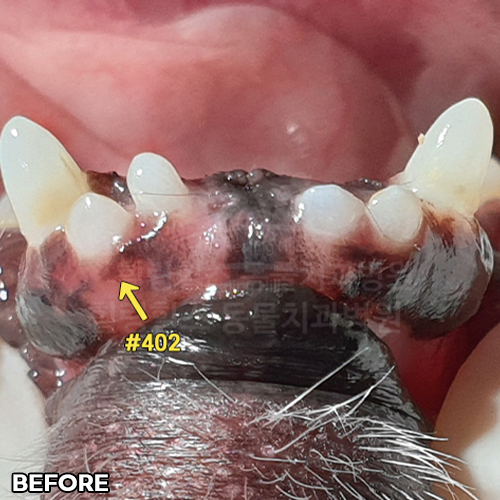

• [강아지 매복치 발치]

[최소침습적 발치 후 2주 경과]

샘플